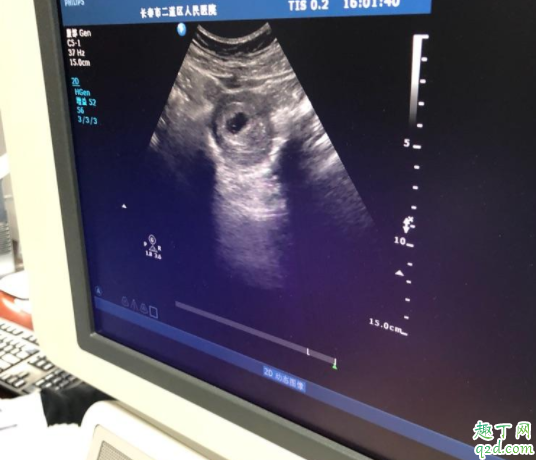

卵黃囊是在懷孕期間妊娠囊中最早出現(xiàn)的結(jié)構(gòu),大概在懷孕5周時(shí)候出現(xiàn)并逐漸增大,給胎芽提供營(yíng)養(yǎng),在12周后逐漸自行消失。

早孕檢查可以做經(jīng)腹部婦科彩超和經(jīng)陰道婦科彩超。兩個(gè)檢查都是同樣的檢查原理,都是利于超聲技術(shù)。只是兩個(gè)檢查的檢查途徑不一樣。經(jīng)腹部婦科超聲需要憋尿,經(jīng)陰道婦科彩超需要排空膀胱。但是經(jīng)陰道婦科彩超干擾更小,能夠早一周看見(jiàn)卵黃囊、胚芽和胎心。